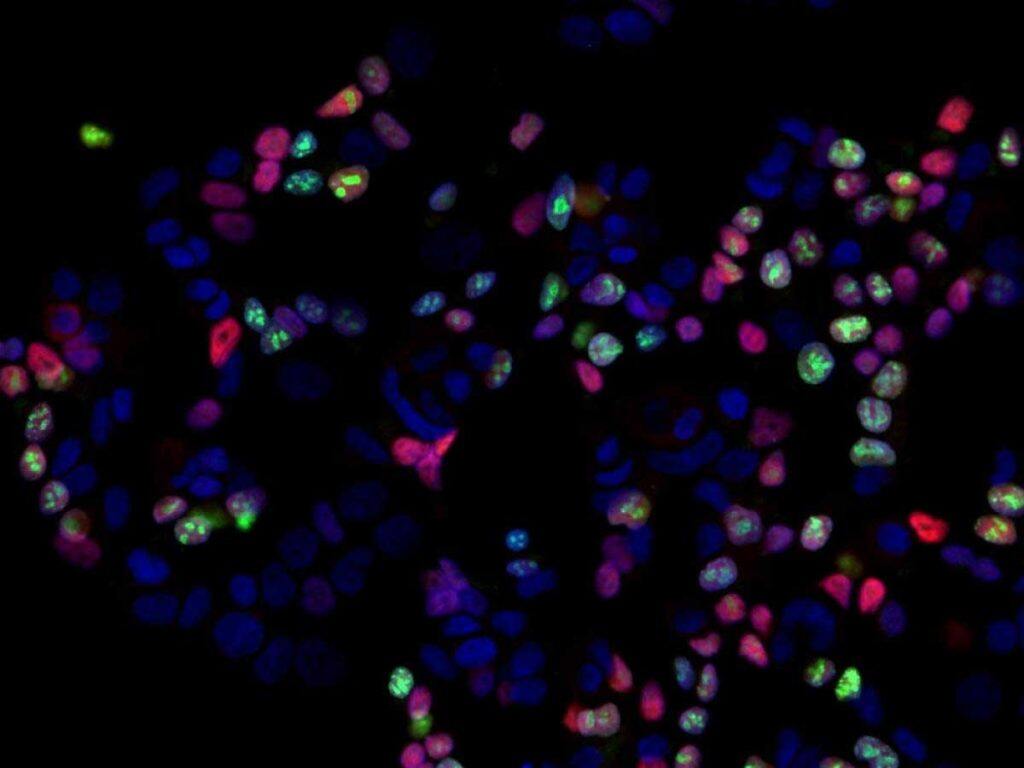

The breast samples were analysed using multiple new technologies to understand the type of cells and genes in the breast tissue that were affected by androgen. This allowed the investigators to understand which cells and genes were altered by the hormone.